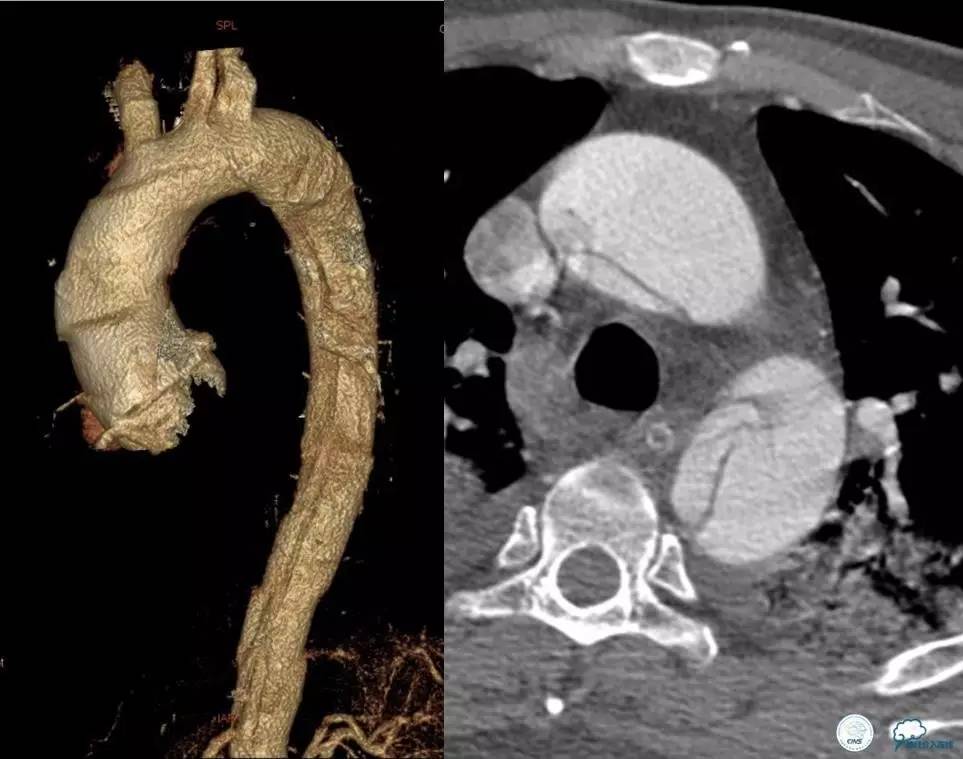

▼主动脉全程CT

中间诊断:

主动脉夹层 De Bakey Ⅰ型

脑梗死

治疗原则:

继续监测血流动力学指标

绝对卧床、控制血压、强效镇静与镇痛

急请血管外科会诊